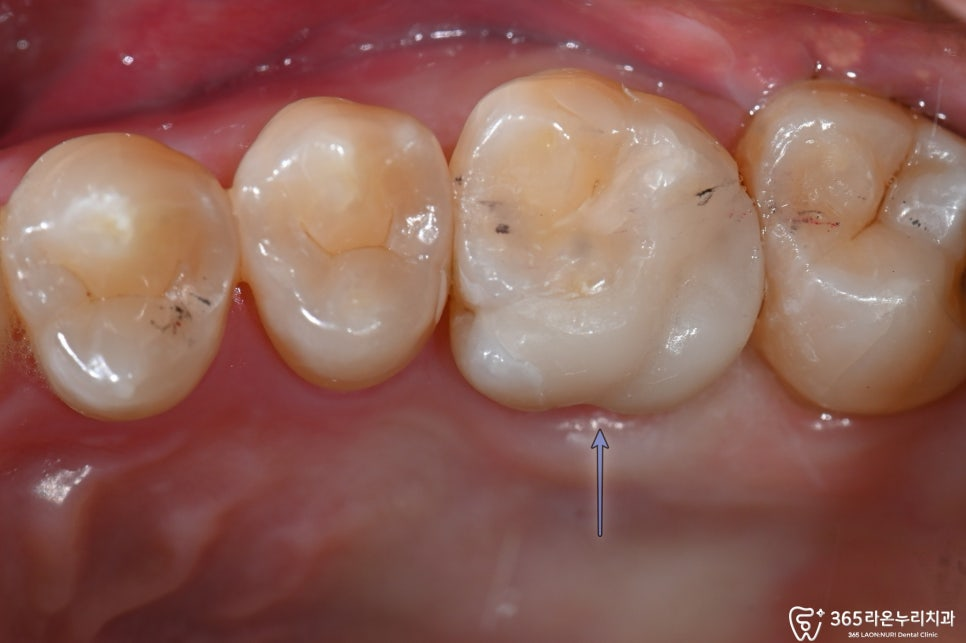

세마동 치과 에서 구강 내 사진을 살펴보면

과거 치료를 받은 모습이 확인되며,

큰 어금니의 보철물이 탈락된 모습을

볼 수 있습니다.

이러한 정황으로 미루어 보아

구강 관리에 어려움이 있어 보이는데요.